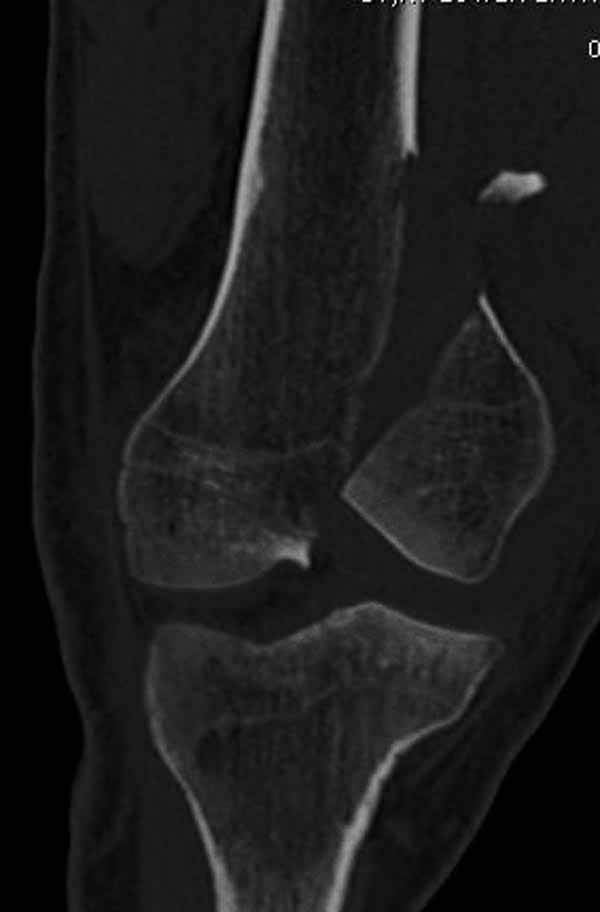

А теперь по поводу лечения перелома. Среди всех чрез/меж-мыщелковых переломов в 38% сопровождются переломом в корональной плоскости, т.е перелом Hoffa. Nork et al, J Orthop Trauma, 87:564, 2005.

У больных как в этом случае, с вовлечением двух мыщелков правильно, что сделали вытяжение до операции. Здесь имеется флексионный компонент на другой стороне, и я бы рекомендовал операцию делать из двух доступов. Сперва фиксировать медиальную колонну custom made пластиной, обычно 1/3 тубулярной пластиной в 4.5 мм, потому что пока производители опаздывают с медиальной пластиной.

Здесь пример медиальной пластины и латеральный комбинированный метод (у второго больного старый перелом тибиал плато, леченный где то и когда то)